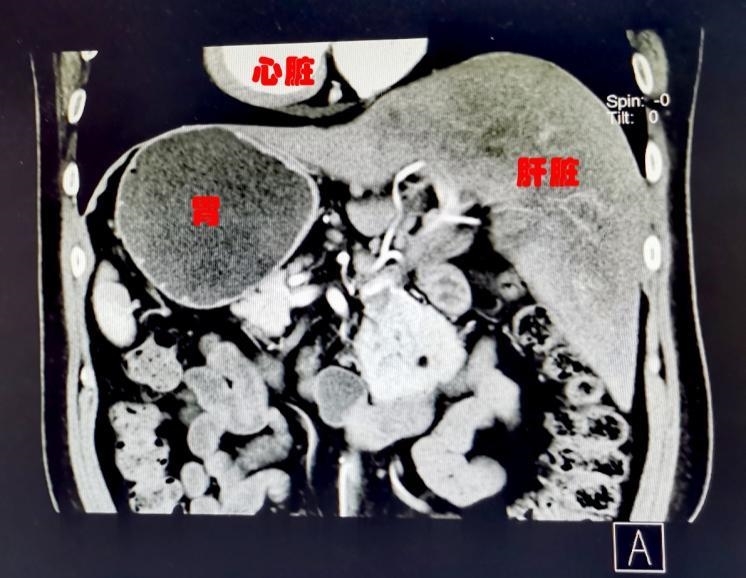

普通人的腹部CT图像

“镜面人”是一种罕见的先天性畸形,患者人体内脏解剖变异,心、肺、横膈、肝、脾、胃、肠等全部内脏的位置呈180度反位。就像正常人照镜子,位置与常人相反,医学上称为“镜面人”。这种畸形通常不影响人的健康,但会给医生治疗,特别是手术治疗造成不小的障碍。